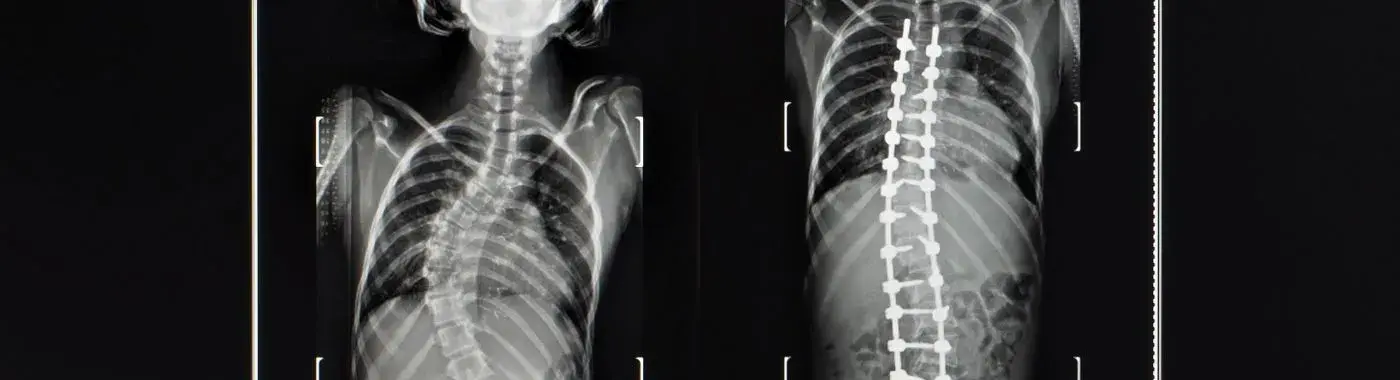

• X-rays: The primary imaging tool used to assess the degree of spinal curvature.

• Surgery: In severe cases, surgical intervention may be necessary to correct the curvature and stabilize the spine. The most common procedure is spinal fusion.